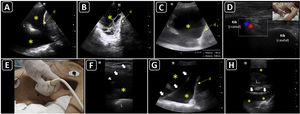

Ultrasound-guided vascular cannulation. A) Preprocedural assessment of a peripheral vein for ultrasound-guided cannulation. The anteroposterior diameter of the vein (continuous yellow line, Distancia 2) and distance from the vein to the skin (continuous green line, Distancia 1) are measured. B) In-plane cannulation of the internal jugular vein (v); arrows, needle shaft; arrowhead, needle tip. C) Out-of-plane cannulation of the internal jugular vein (v); a, common carotid artery; arrow, needle. D) The guidewire is observed in the vein lumen (arrows) before placement of a long catheter in the basilic vein (e.g., midline catheter); v, vein. E) A peripheral venous catheter (arrow) is observed in the lumen of a deep vein of the arm (short axis); v, brachial veins; a, brachial artery. F) A peripheral catheter (arrows) is depicted in the lumen of a superficial vein in the long axis; v, vein. G) Subperiostial flow is observed on color Doppler after intraosseous needle insertion. H) Pseudoaneurysm as a complication of femoral arterial catheterization; black arrows, pseudoaneurysm cavity; white arrows, pseudoaneurysm neck; a, common femoral artery; v, common femoral vein.

After disinfecting the skin and applying a local anesthetic under real-time ultrasound guidance, the needle is inserted in-plane or out-of-plane (Fig. 1B and C), and the catheter is accommodated using the trocar or Seldinger technique. When using the latter, the guidewire should be confirmed in the vessel before progressing the dilator (Fig. 1D).

To assess the CVC tip position, one operator injects agitated saline or normal saline through the distal port of the CVC, while a second operator performs simultaneously a subcostal 4 chamber view or an apical 4 chamber view. The immediate (within 2 s) appearance of turbulent flow in the right atrium is known as the rapid atrial swirl sign (RASS) and predicts with excellent sensitivity and specificity for a correct catheter tip positioning45 (Video 1).

The intravenous position of a peripheral catheter is assessed by direct visualization in the short and/or long axis (Fig. 1E and F) and the flush test (Video 2).

Intraosseous cannulation is not performed under real-time ultrasound guidance; however, its correct position may be evaluated using color Doppler when subperiosteal flow is observed after flushing the line (Fig. 1G).47

PosprocedurePOCUS is performed to assess complications, such as hematoma, pneumothorax (rechecking the lung sliding), infiltration, and catheter-related thrombosis. The distal flow should also be assessed after arterial cannulations, while a pseudoaneurysm should be ruled out (Fig. 1H), when the catheter is removed.